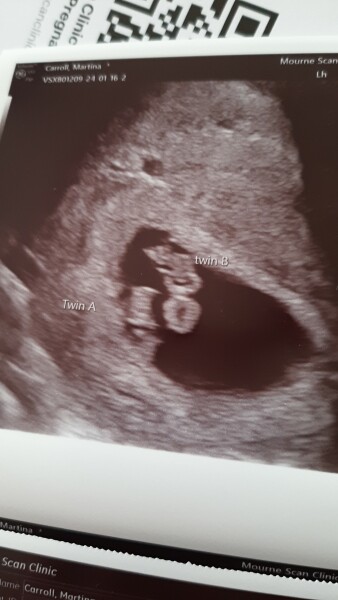

Hello! My due date is September 3rd. Found out at 7 weeks it's TWINS 😊 already have a 3 year old daughter, our car and house seem so small now knowing 2 more people joining us.

Still feels surreal that's there's twins! I'm in Ireland, I paid for a private scan at 7 weeks, both twins measuring the same. It will be high risk as they are in the same sac. I think that means identical too. I didn't really ask too many questions!

My "big" scan is the 1st of March which seems like forever away. I'm very tired but craving meat/protein which is good. I'm the same size as what I was 4 months pregnant with my daughter :/ . I'm just shy of 10 weeks now.